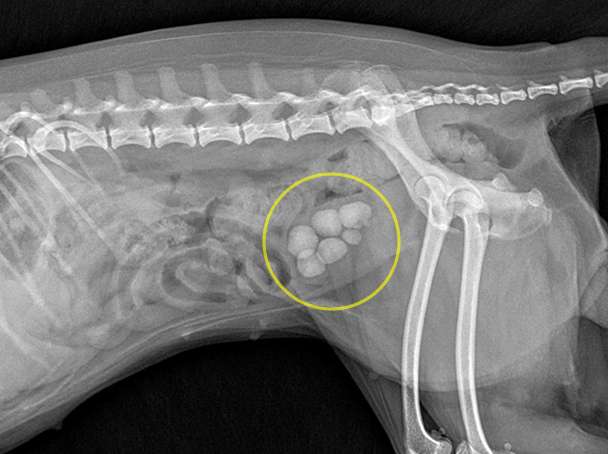

포인트 방광결석수술 케이스

방광결석의 경우 요도결석으로 진행되거나, 방광염을 유발하고 통증을 일으키므로

수술로 제거해야 합니다. 수술 후에는 결석 종류를 찾고 그에 맞는 약물,식이관리로

이후 재발을 막아야 합니다.